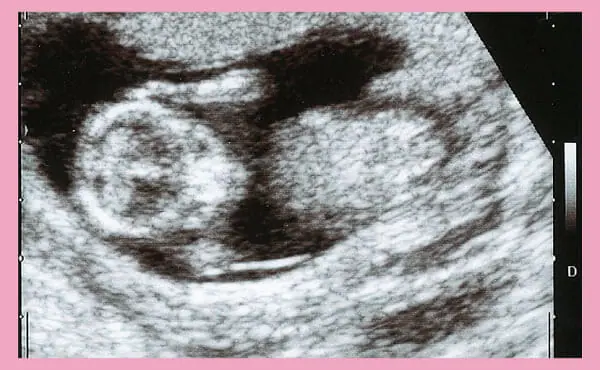

This is an ultrasound image at the 13th week of pregnancy.